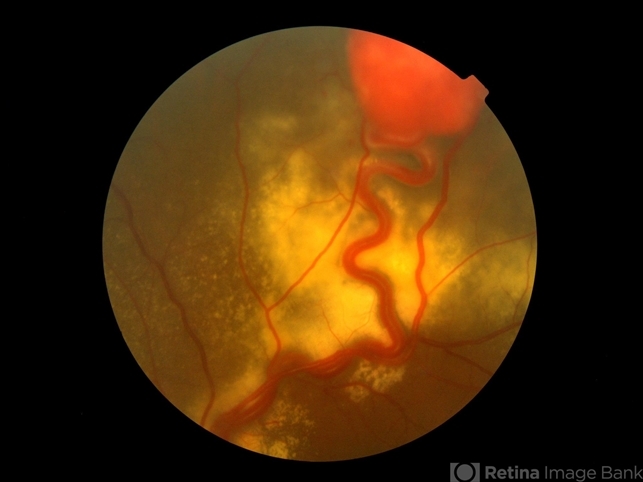

- retinal angiomatous proliferation (RAP)

- Color fundus photograph of a 35-year-old woman with retinal angiomatosis.